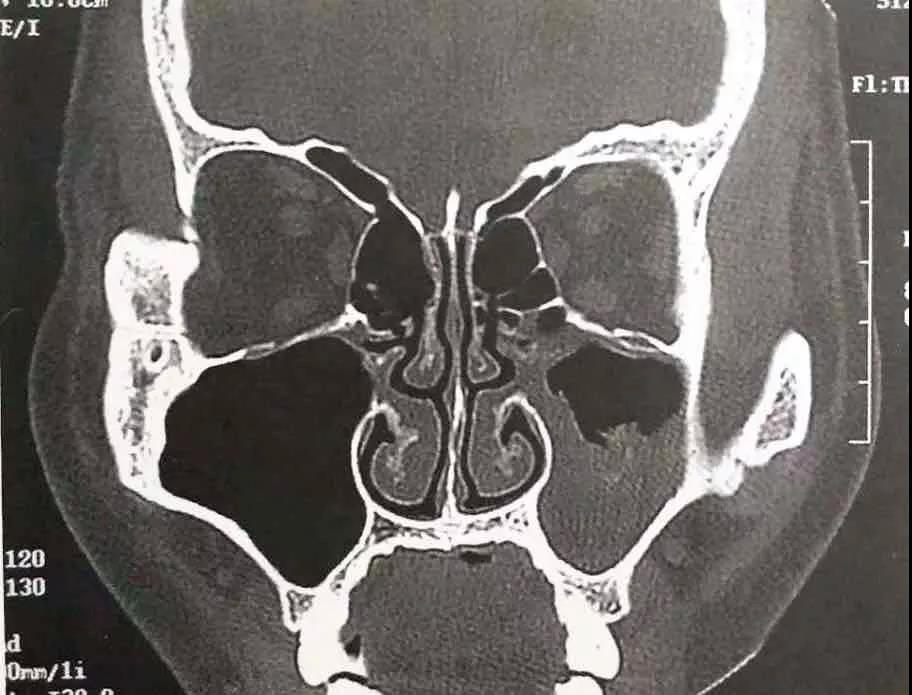

之后一個月,魏大叔仍然斷斷續(xù)續(xù)聞到難聞的異味,在雅安某醫(yī)院進行副鼻竇CT檢查后,診斷為鼻竇炎。

(魏大叔CT圖示)